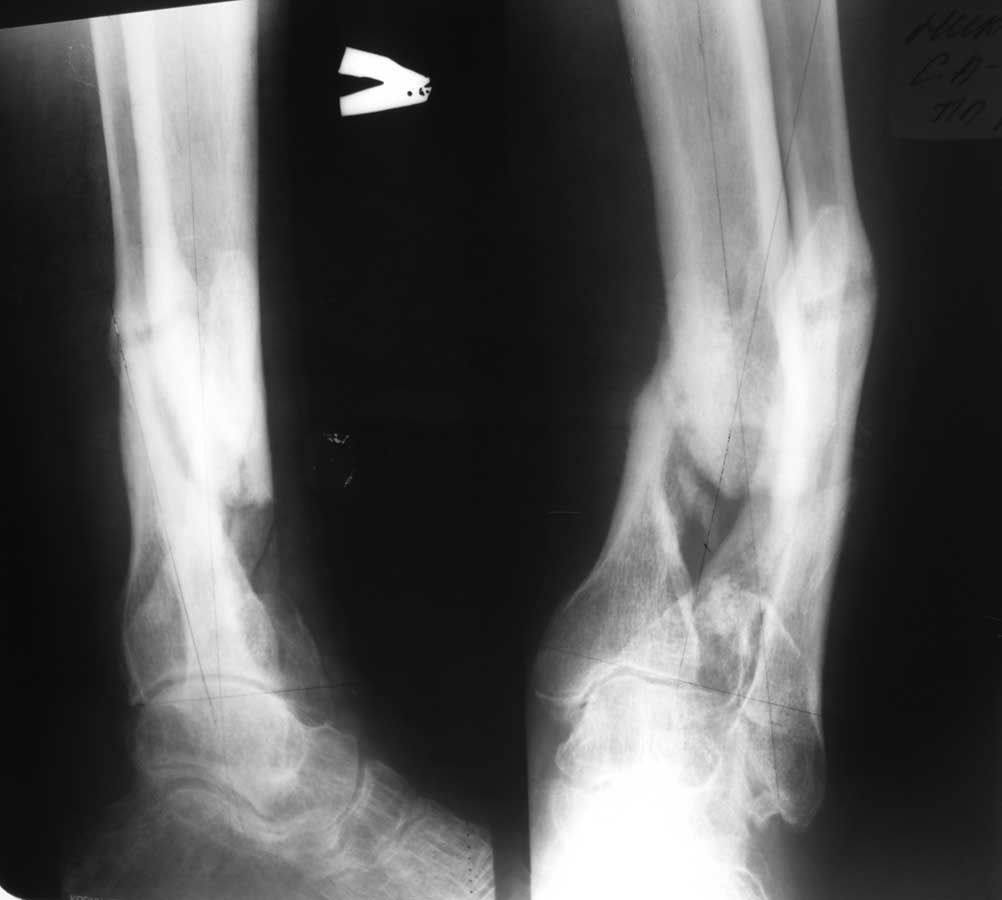

Re: Ложный сустав голени

Дмитрий 08 Октябрь 2011, 22:38

Уважаемый Александр Николаевич! Вот фото рентгенограмм.